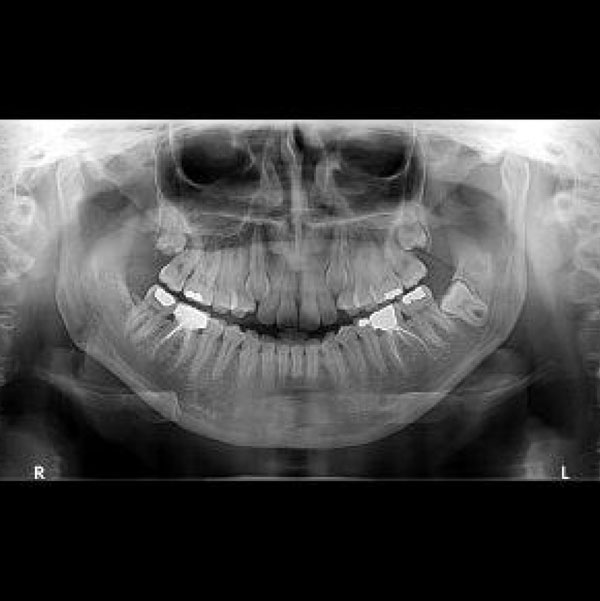

Digital Dental X-Rays

Dental x-rays are essential preventative diagnostic tools that provide valuable information not otherwise visible during a dental exam. Dentists and dental hygienists use this information to safely and accurately detect hidden dental abnormalities and create an appropriate treatment plan. Without x-rays, problem areas may go undetected.

3D Digital CT scanner by Carestream:

Get the most advanced x-rays in the state with a digital 3D Cone Beam at Flat Rate Doctors! We are proud to be one of the few offices in the state of Utah to offer 3D Cone Beams to our patients. CT images can be used to help with wisdom teeth extractions, placement of implants and a wide array of dental treatments along with use for our chiropractic services for cervical neck x-rays.

Dental x-rays may reveal:

Abscesses or cysts

Bone loss

Cancerous and non-cancerous tumors

Decay between the teeth

Developmental abnormalities

Poor tooth and root positions

Problems inside a tooth or below the gum line

Detecting and treating dental problems at an early stage can save you time, money, unnecessary discomfort, and may even save your teeth from eventually being lost to decay or periodontal disease.

Are dental x-rays safe?

Dental x-rays produce a low level of radiation and are considered safe. Our office uses digital x-rays that have lower radiation amounts than traditional x-rays. The amount of radiation exposure from a full mouth series of x-rays is equal to the amount a person receives in a single day from natural sources. Nevertheless, dentists do take precautions to limit the patient’s exposure to radiation when taking digital x-rays. These precautions include using lead apron shields to protect the body and using modern, fast film that cuts down the exposure time of each x-ray.

How often should dental x-rays be taken?

The need for dental x-rays depends on each patient’s individual dental health needs. Your dentist and dental hygienist will recommend necessary x-rays based on the review of your medical and dental history, dental exam, signs and symptoms, age consideration, and risk for disease.

A full mouth series of dental x-rays is recommended for new patients. A full series is usually good for three to five years. Bite-wing x-rays (x-rays of top and bottom teeth biting together) and are recommended once or twice a year at your as part of your dental check